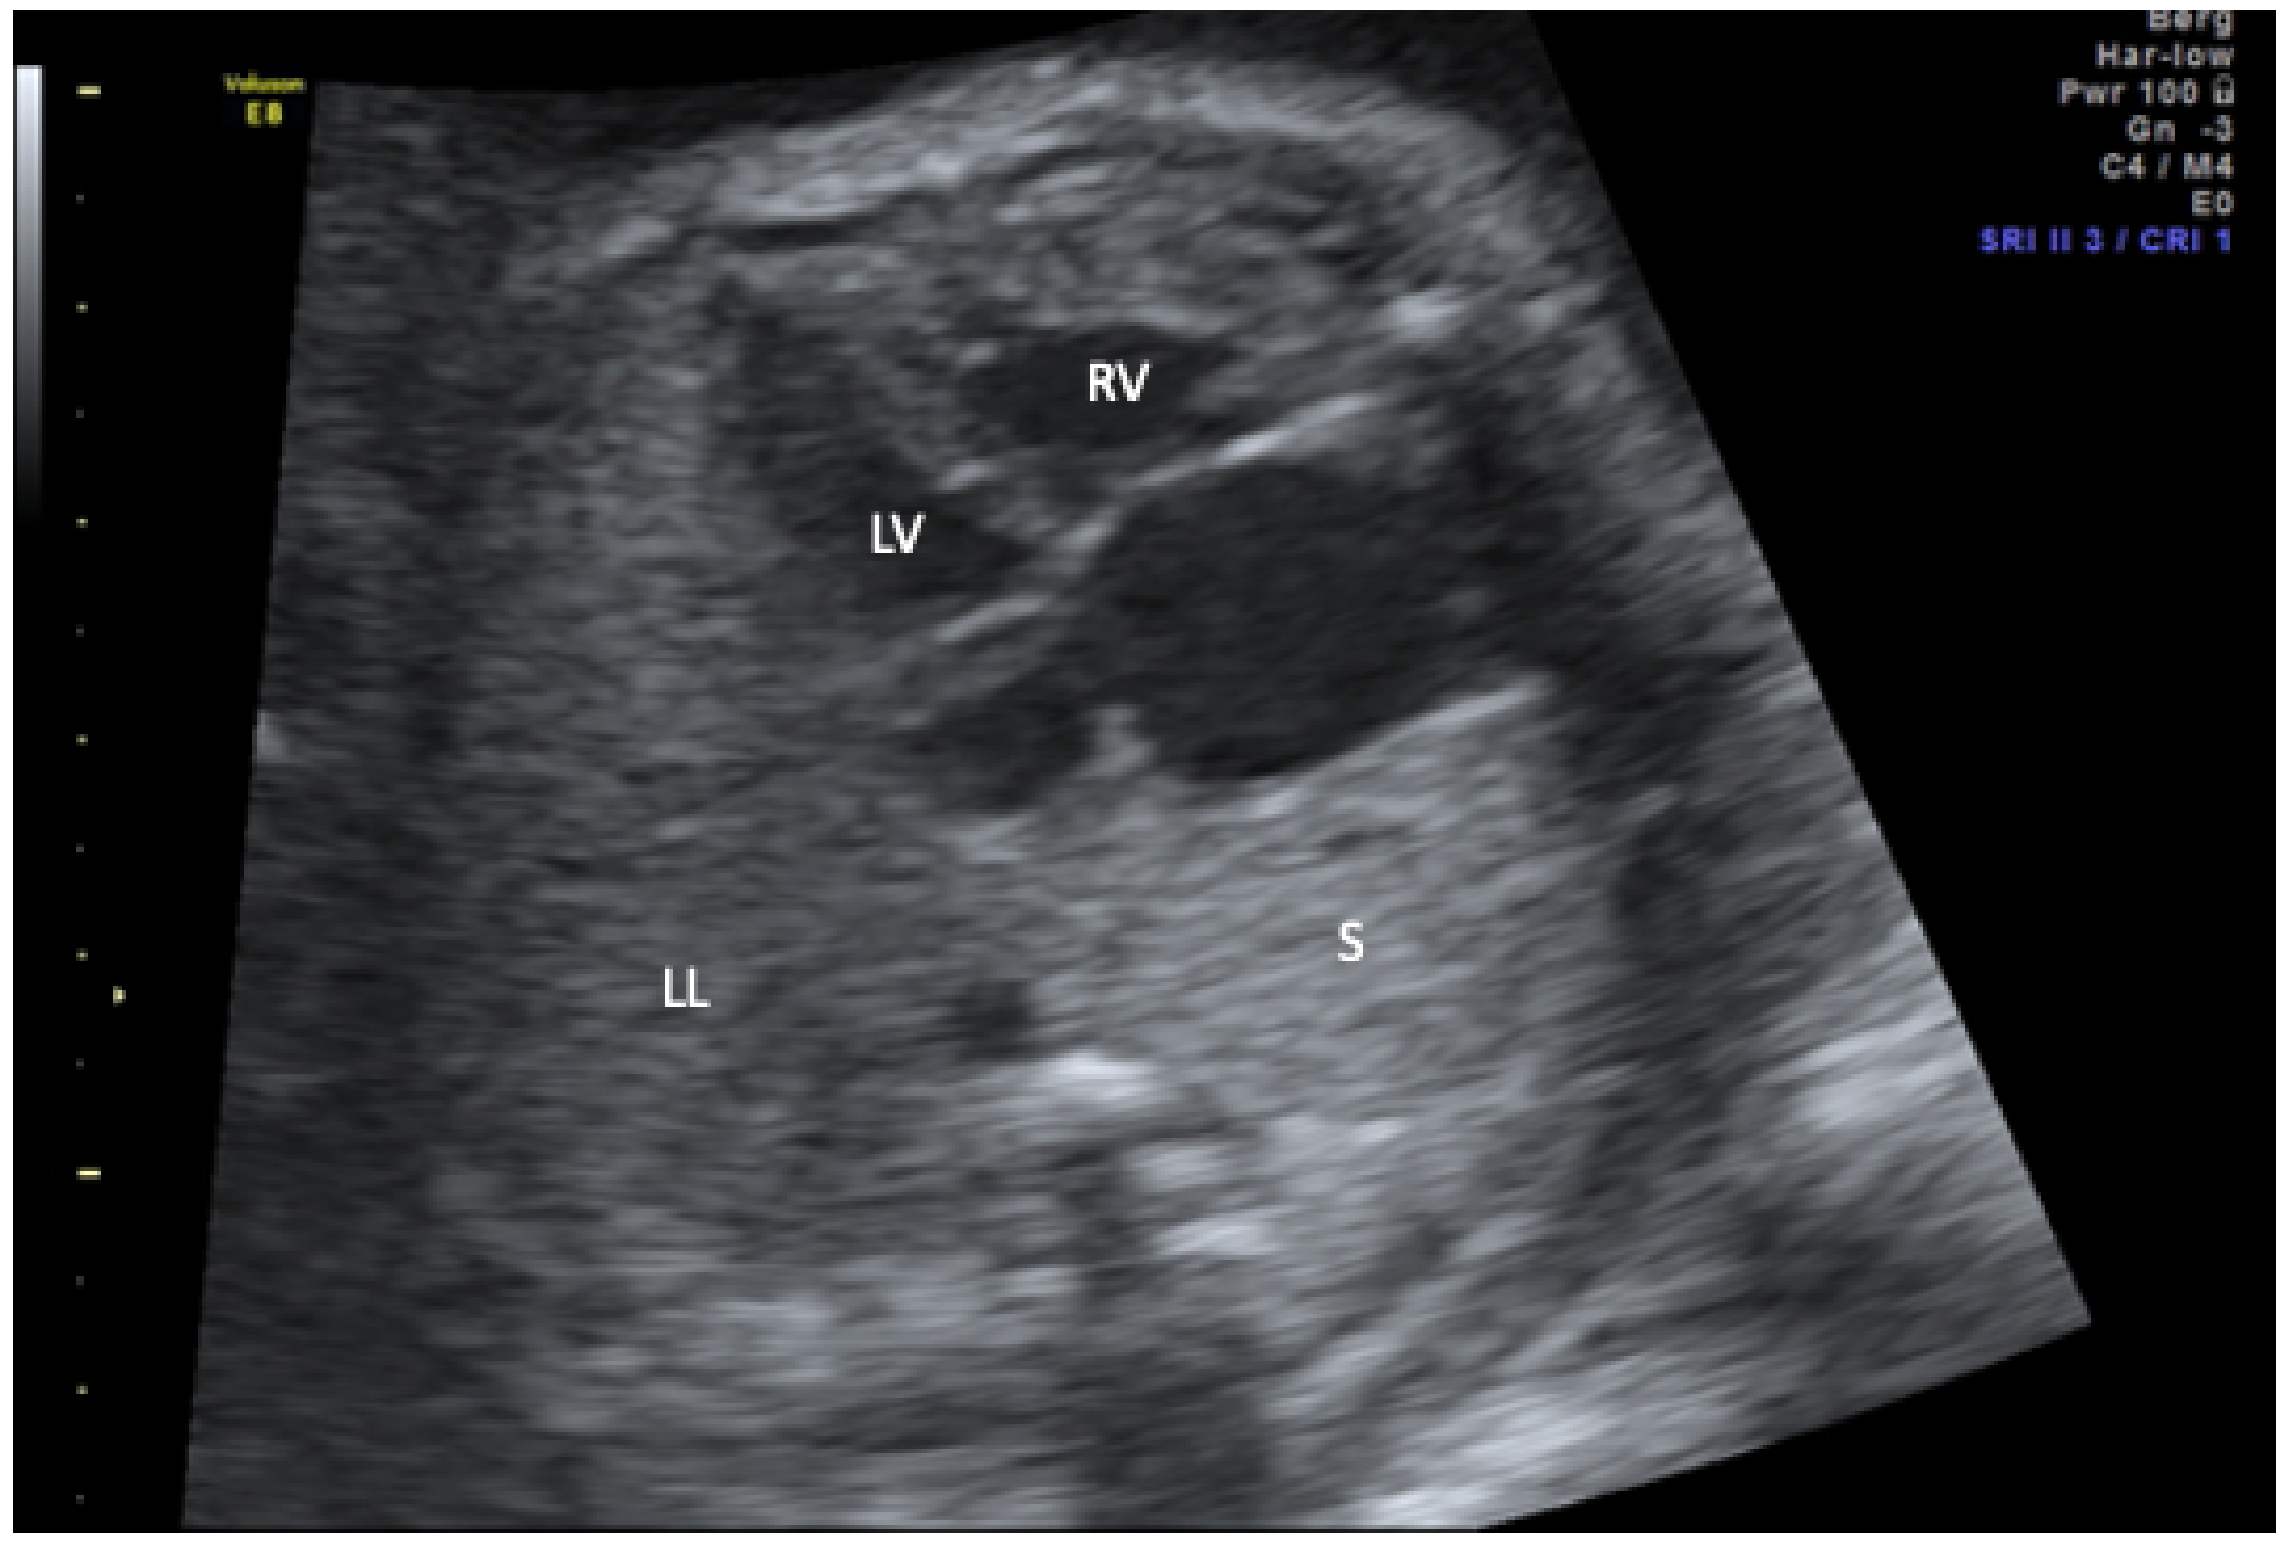

| 1 | 34 + 1 | mediastinal shift; dextroposition of the heart, right pulmonary hypoplasia, partial anomalous pulmonary drainage (scimitar vein) | 39 + 1 | Feeding vessel from coeliac trunk, secundum atrial septal defect | Coil occlusion of feeding vessel, pulmonary hemorrhage with respiratory deterioration, intracranial hemorrhage, diabetes insipidus centralis, exitus at 1 month |

| 2 | 38 + 0 | mediastinal shift; dextroposition of the heart, right pulmonary hypoplasia, partial, anomalous pulmonary drainage (scimitar vein), right sided diaphragmatic hernia; coarctation; duplication 10q22.1–10q23.2 | 39 + 2 | Feeding vessel from abdominal aorta, pulmonary hypertension | Coil occlusion of feeding vessel, intractable pulmonary hypertension, exitus at 6 months |

| 3 | 20 + 2 | mediastinal shift; dextroposition of the heart, right pulmonary hypoplasia, partial anomalous pulmonary drainage (scimitar vein) | 35 + 5 | Feeding vessel from abdominal aorta, hypoplastic aortic arch; secundum atrial septal defect; anomalous supracardiac pulmonary drainage of left pulmonary veins in brachiocephalic vein | Plug occlusion of feeding vessel, reinsertion of left pulmonary veins, patch reconstruction of aortic arch, postoperative hydrocephalus; hypoplastic corpus callosum; ventilation malfunction hypoxic crisis with bradyasystole, exitus at 6 months, |

| 4 | 31 + 1 | mediastinal shift; dextroposition of the heart, right pulmonary hypoplasia, anal atresia, diaphragmatic hernia, hemivertebrae, single umbilical artery, renal dysplasia | 33 + 6 | partial anomalous pulmonary drainage (scimitar vein), Feeding vessels from thoracic aorta, hypoplastic aortic arch, secundum atrial septal defect, VACTERL association | Plug occlusion of feeding vessel and 2 MAPCAs in neonatal period, multiple bronchial stent placements, 4 years old |

| 5 | 22 + 2 | mediastinal shift; dextroposition of the heart, right pulmonary hypoplasia, partial anomalous pulmonary drainage (scimitar vein) | 31 + 0 | Feeding vessel from coeliac trunk, secundum atrial septal defect, mild coarctation | Plug occlusion of feeding vessels in neonatal period, thriving with mild pulmonary hypertension, 7 years old |

| 6 | 17 + 2 | mediastinal shift; dextroposition of the heart, right pulmonary hypoplasia, partial anomalous pulmonary drainage (scimitar vein), single umbilical artery, left persistent superior caval vein | 40 + 0 | 2 Feeding vessels from thoracic aorta, anomalous drainage of right sided pulmonary veins in left atrium, secundum atrial septal defect | Plug occlusion of feeding vessels in neonatal period and at age of one year. Correction of right pulmonary veinous drainage with intra-atrial tunnel and ligation of persisting ductus arteriosus at age of 2 years, infantile cerebral palsy; tracheostoma; Percutaneous endoscopic gastrostomy(PEG) placement, 10 years old |